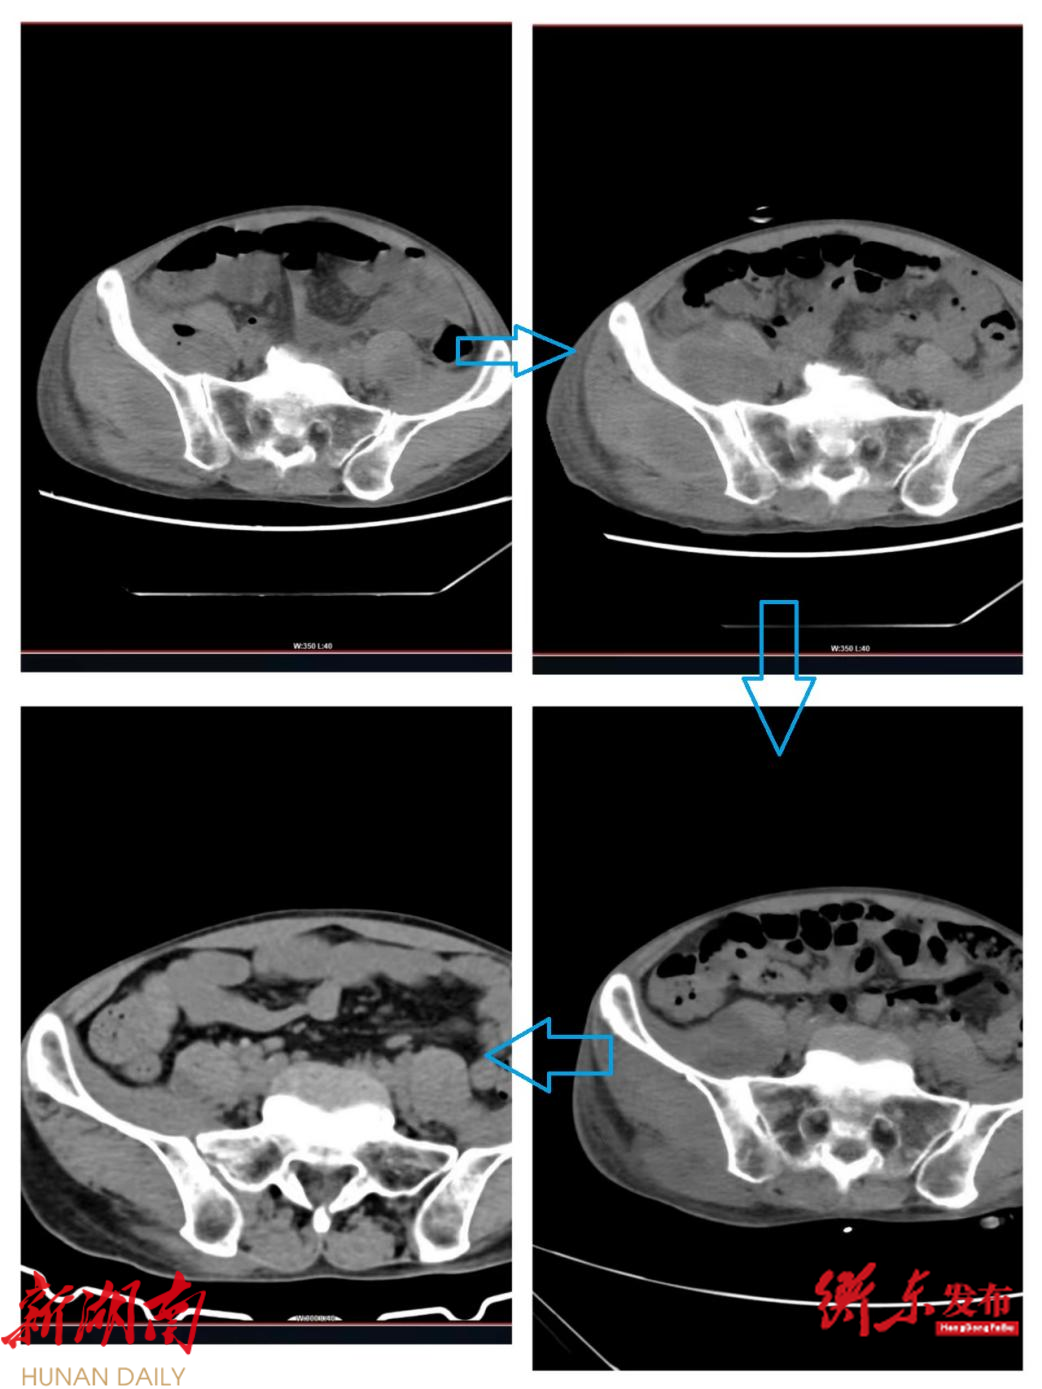

经检查,患者的CT提示全身多发脓肿并产气,但病因暂时不明确。为了明确病因,南华医院全科医学科组织医院重症医学科、放射科、感染科、介入血管外科、消化内科、检验科等多学科开展会诊,协作诊疗病人。

经过仔细询问患者病史及职业等情况,发现患者每天均会生食朝天椒,并且他的职业也是备餐员,经常会接触海鲜等生食,极易污染。根据这些情况,血培养结果提示可能存在沙门菌感染。通过南华医院多学科的通力协作,终于揭开了颜先生患病的“谜团”。但是患者多发脓肿,他也并非一次性大量接触沙门菌,这说明并非急性沙门菌感染,全科团队考虑可能是少量多次感染沙门菌所致。

在明确病因后,医院对患者进行了多次引流,并联合抗生素治疗和营养支持治疗。这些措施取得了显著效果,患者的多项症状得到了明显缓解,各项指标也恢复正常。经过顺利地治疗康复,颜先生终于可以出院了。南华医院全科医学科也将进行定期的随访工作,以确保患者的健康稳定。